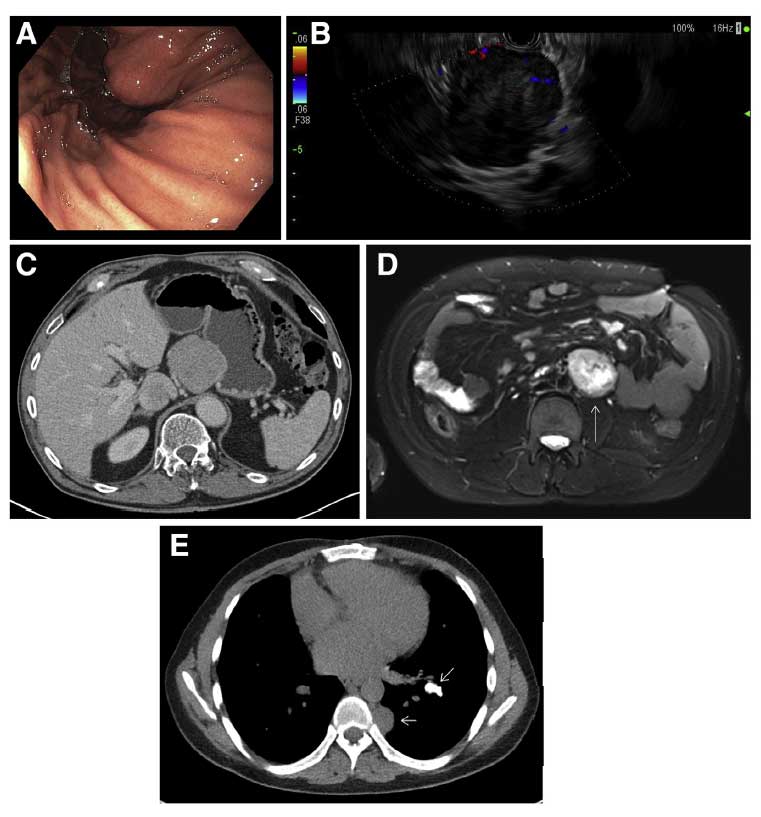

QUIZ: Tumores múltiplos em um paciente jovem